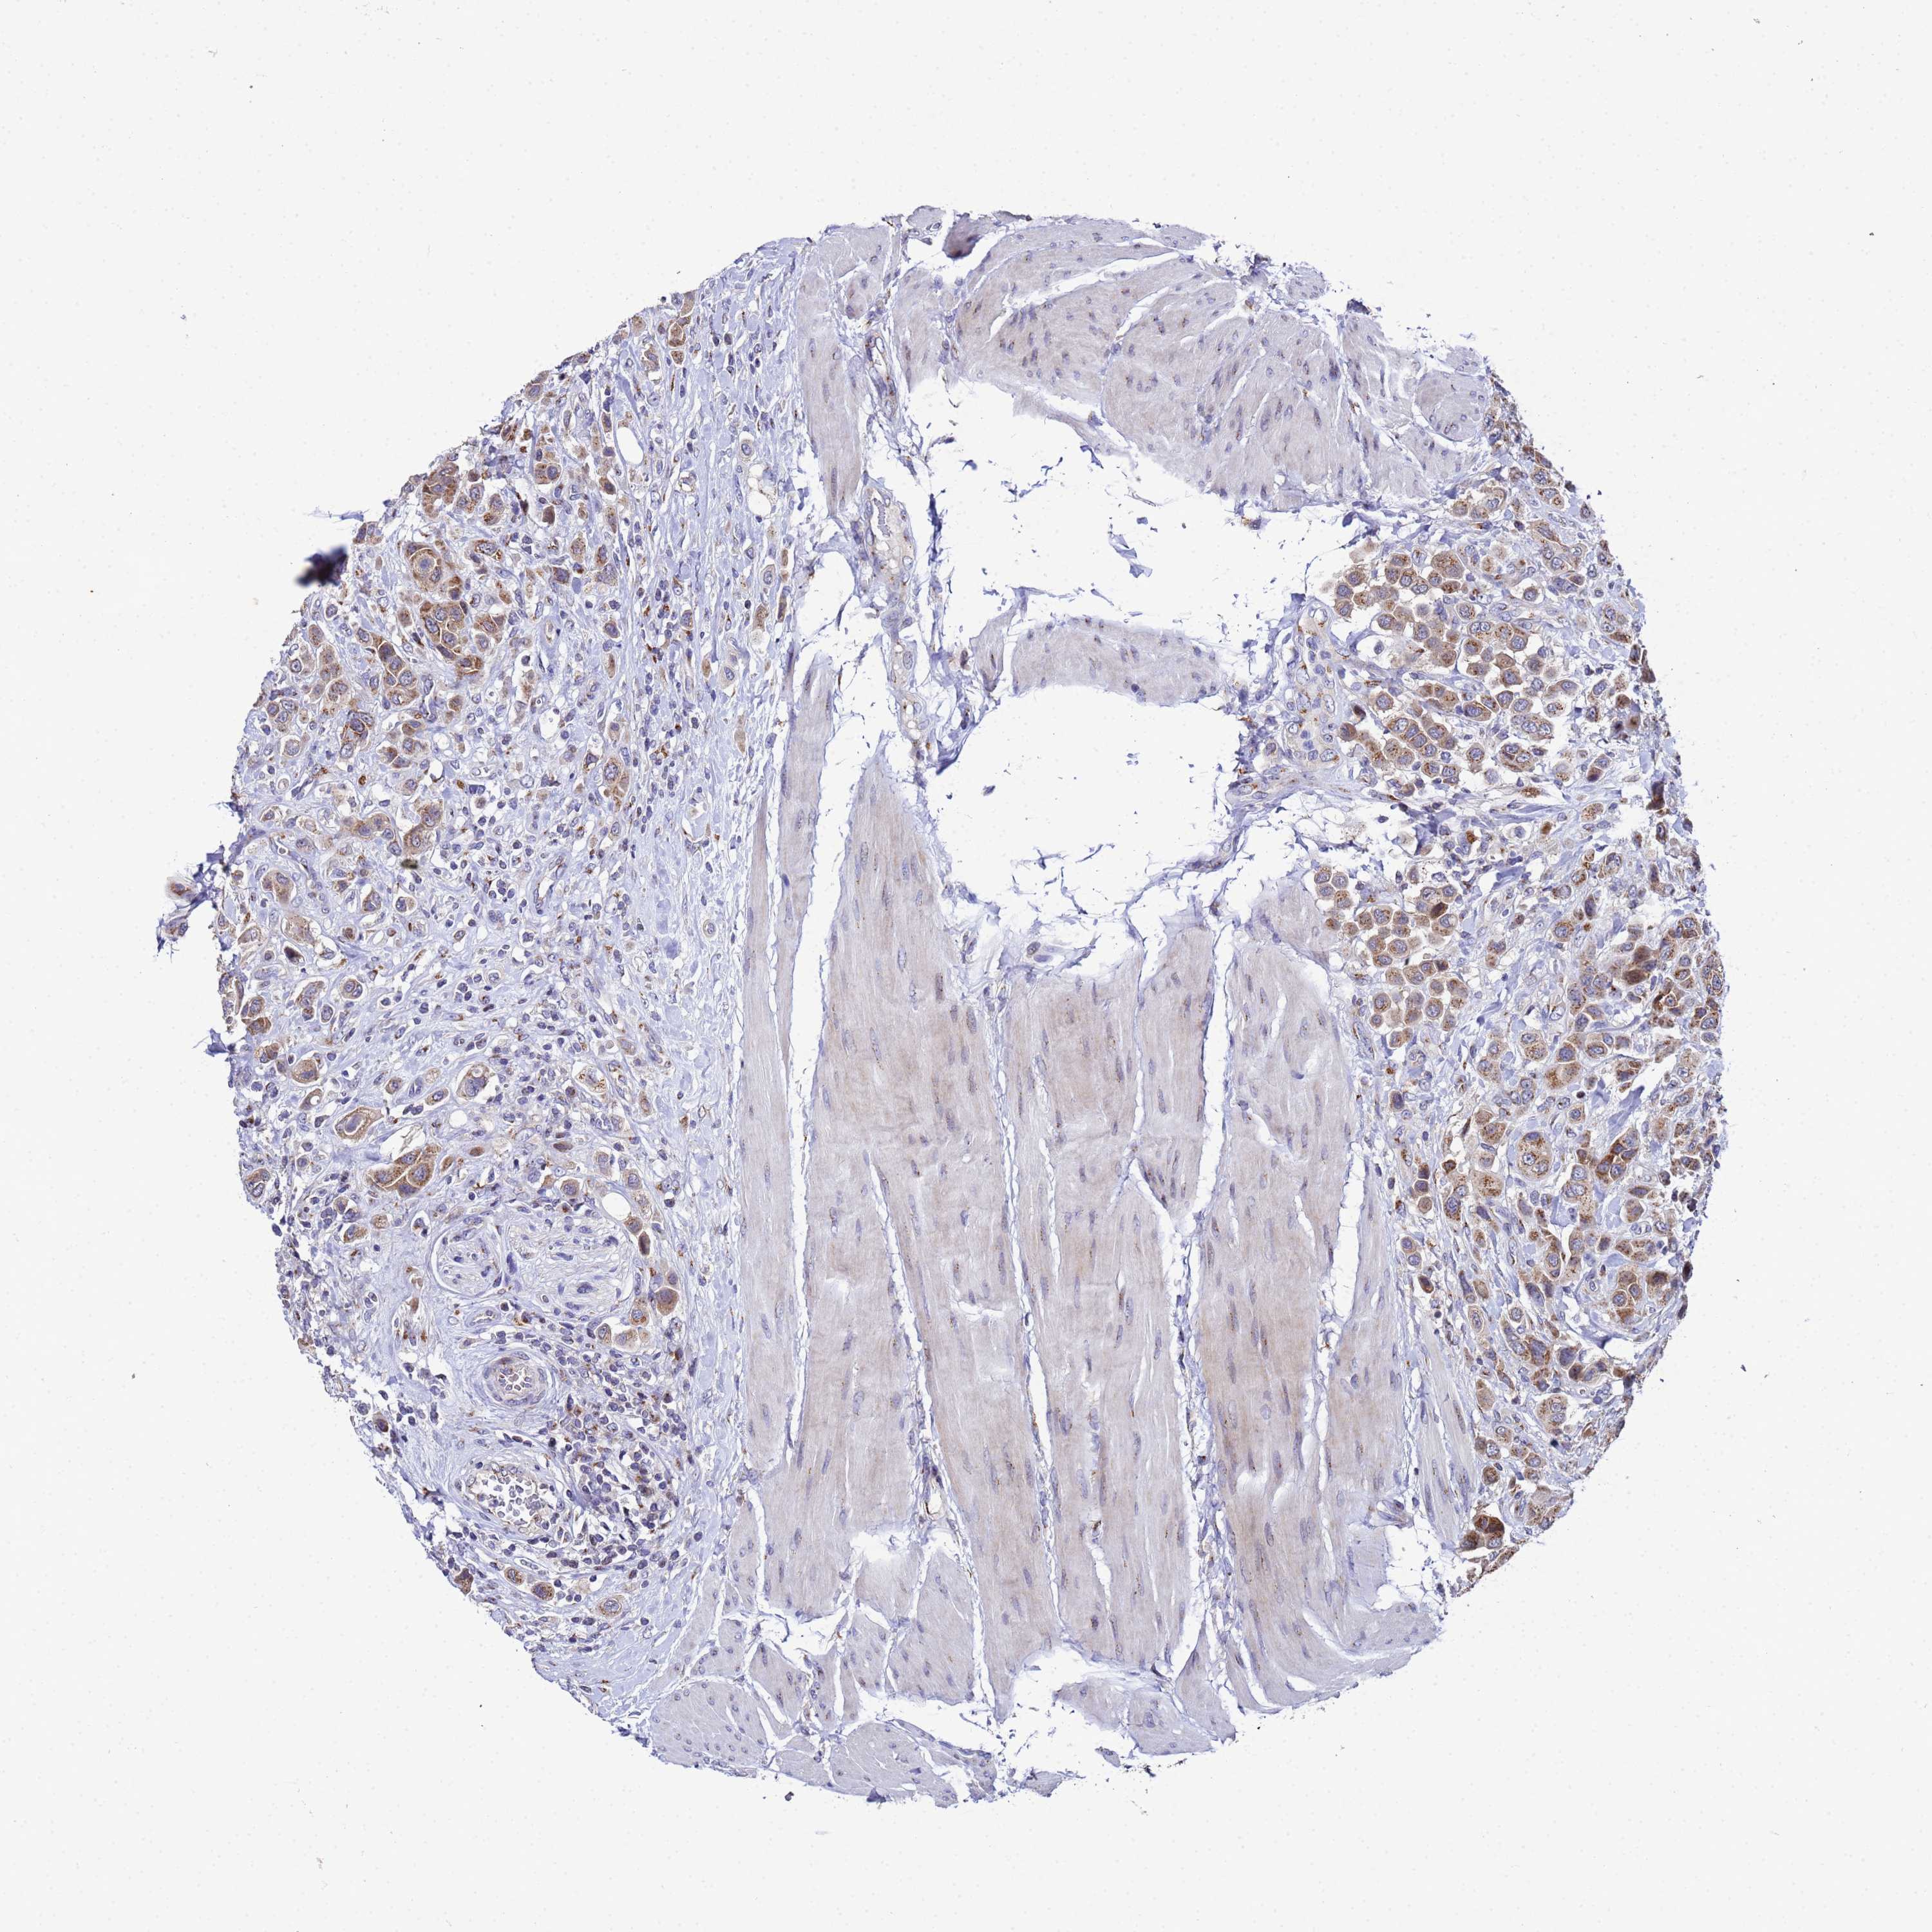

UROTHELIAL CANCER - Protein expressioni

A mouse-over function shows sample information and annotation data. Click on an image to view it in a full screen mode. Samples can be filtered based on level of antibody staining by selecting one or several of the following categories: high, medium, low and not detected. The assay and annotation is described here.

Note that samples used for immunohistochemistry by the Human Protein Atlas do not correspond to samples in the TCGA dataset.

Antibody stainingi

Antibody staining in the annotated cell types in the current human tissue is reported as not detected, low, medium, or high, based on conventional immunohistochemistry profiling in selected tissues. This score is based on the combination of the staining intensity and fraction of stained cells.

Each image is clickable and will lead to virtual microscopy that enables deeper exploration of all samples and also displays staining intensity scores, fraction scores and subcellular localization as well as patient and tissue information for each sample.

Antibody HPA045902

Staining

High

Medium

Low

Not detected

Intensity

Strong

Moderate

Weak

Negative

Quantity

>75%

75%-25%

<25%

None

Location

Nuclear

Cytoplasmic/membranous

Cytoplasmic/membranous,nuclear

Urothelial carcinoma, High grade

Urothelial carcinoma, Low grade